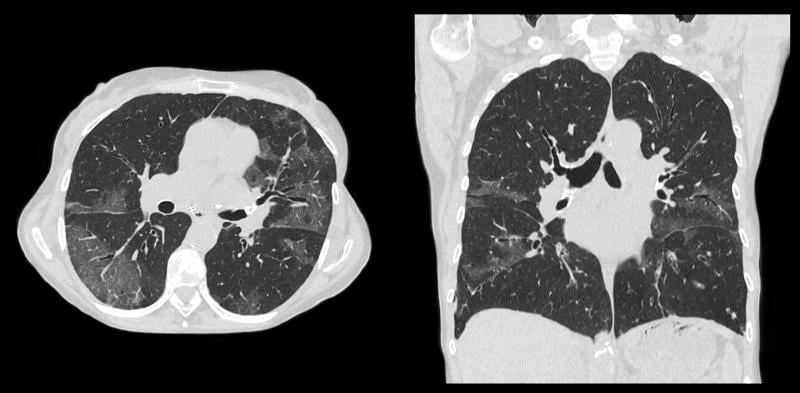

This photo gallery shows the variety of radiological presentations of COVID-19 (SARS-CoV-2) in medical imaging, including computed tomography (CT), radiograph X-rays, ultrasound, echocardiograms and magnetic resonance imaging (MRI). The radiology images show examples of typical COVID pneumonia in the lungs and the numerous complications the virus causes in the body in multiple organs, including the brain, kidneys, heart, abdomen and vascular system.

Ultrasound, especially hand-held ultrasound imaging devices, have become a primary imaging modality for novel coronavirus because of the ease to bag the device and sterilize it after use. CT and mobile X-ray systems are also used as front-line imaging systems for COVID-positive or suspected COVID patients.